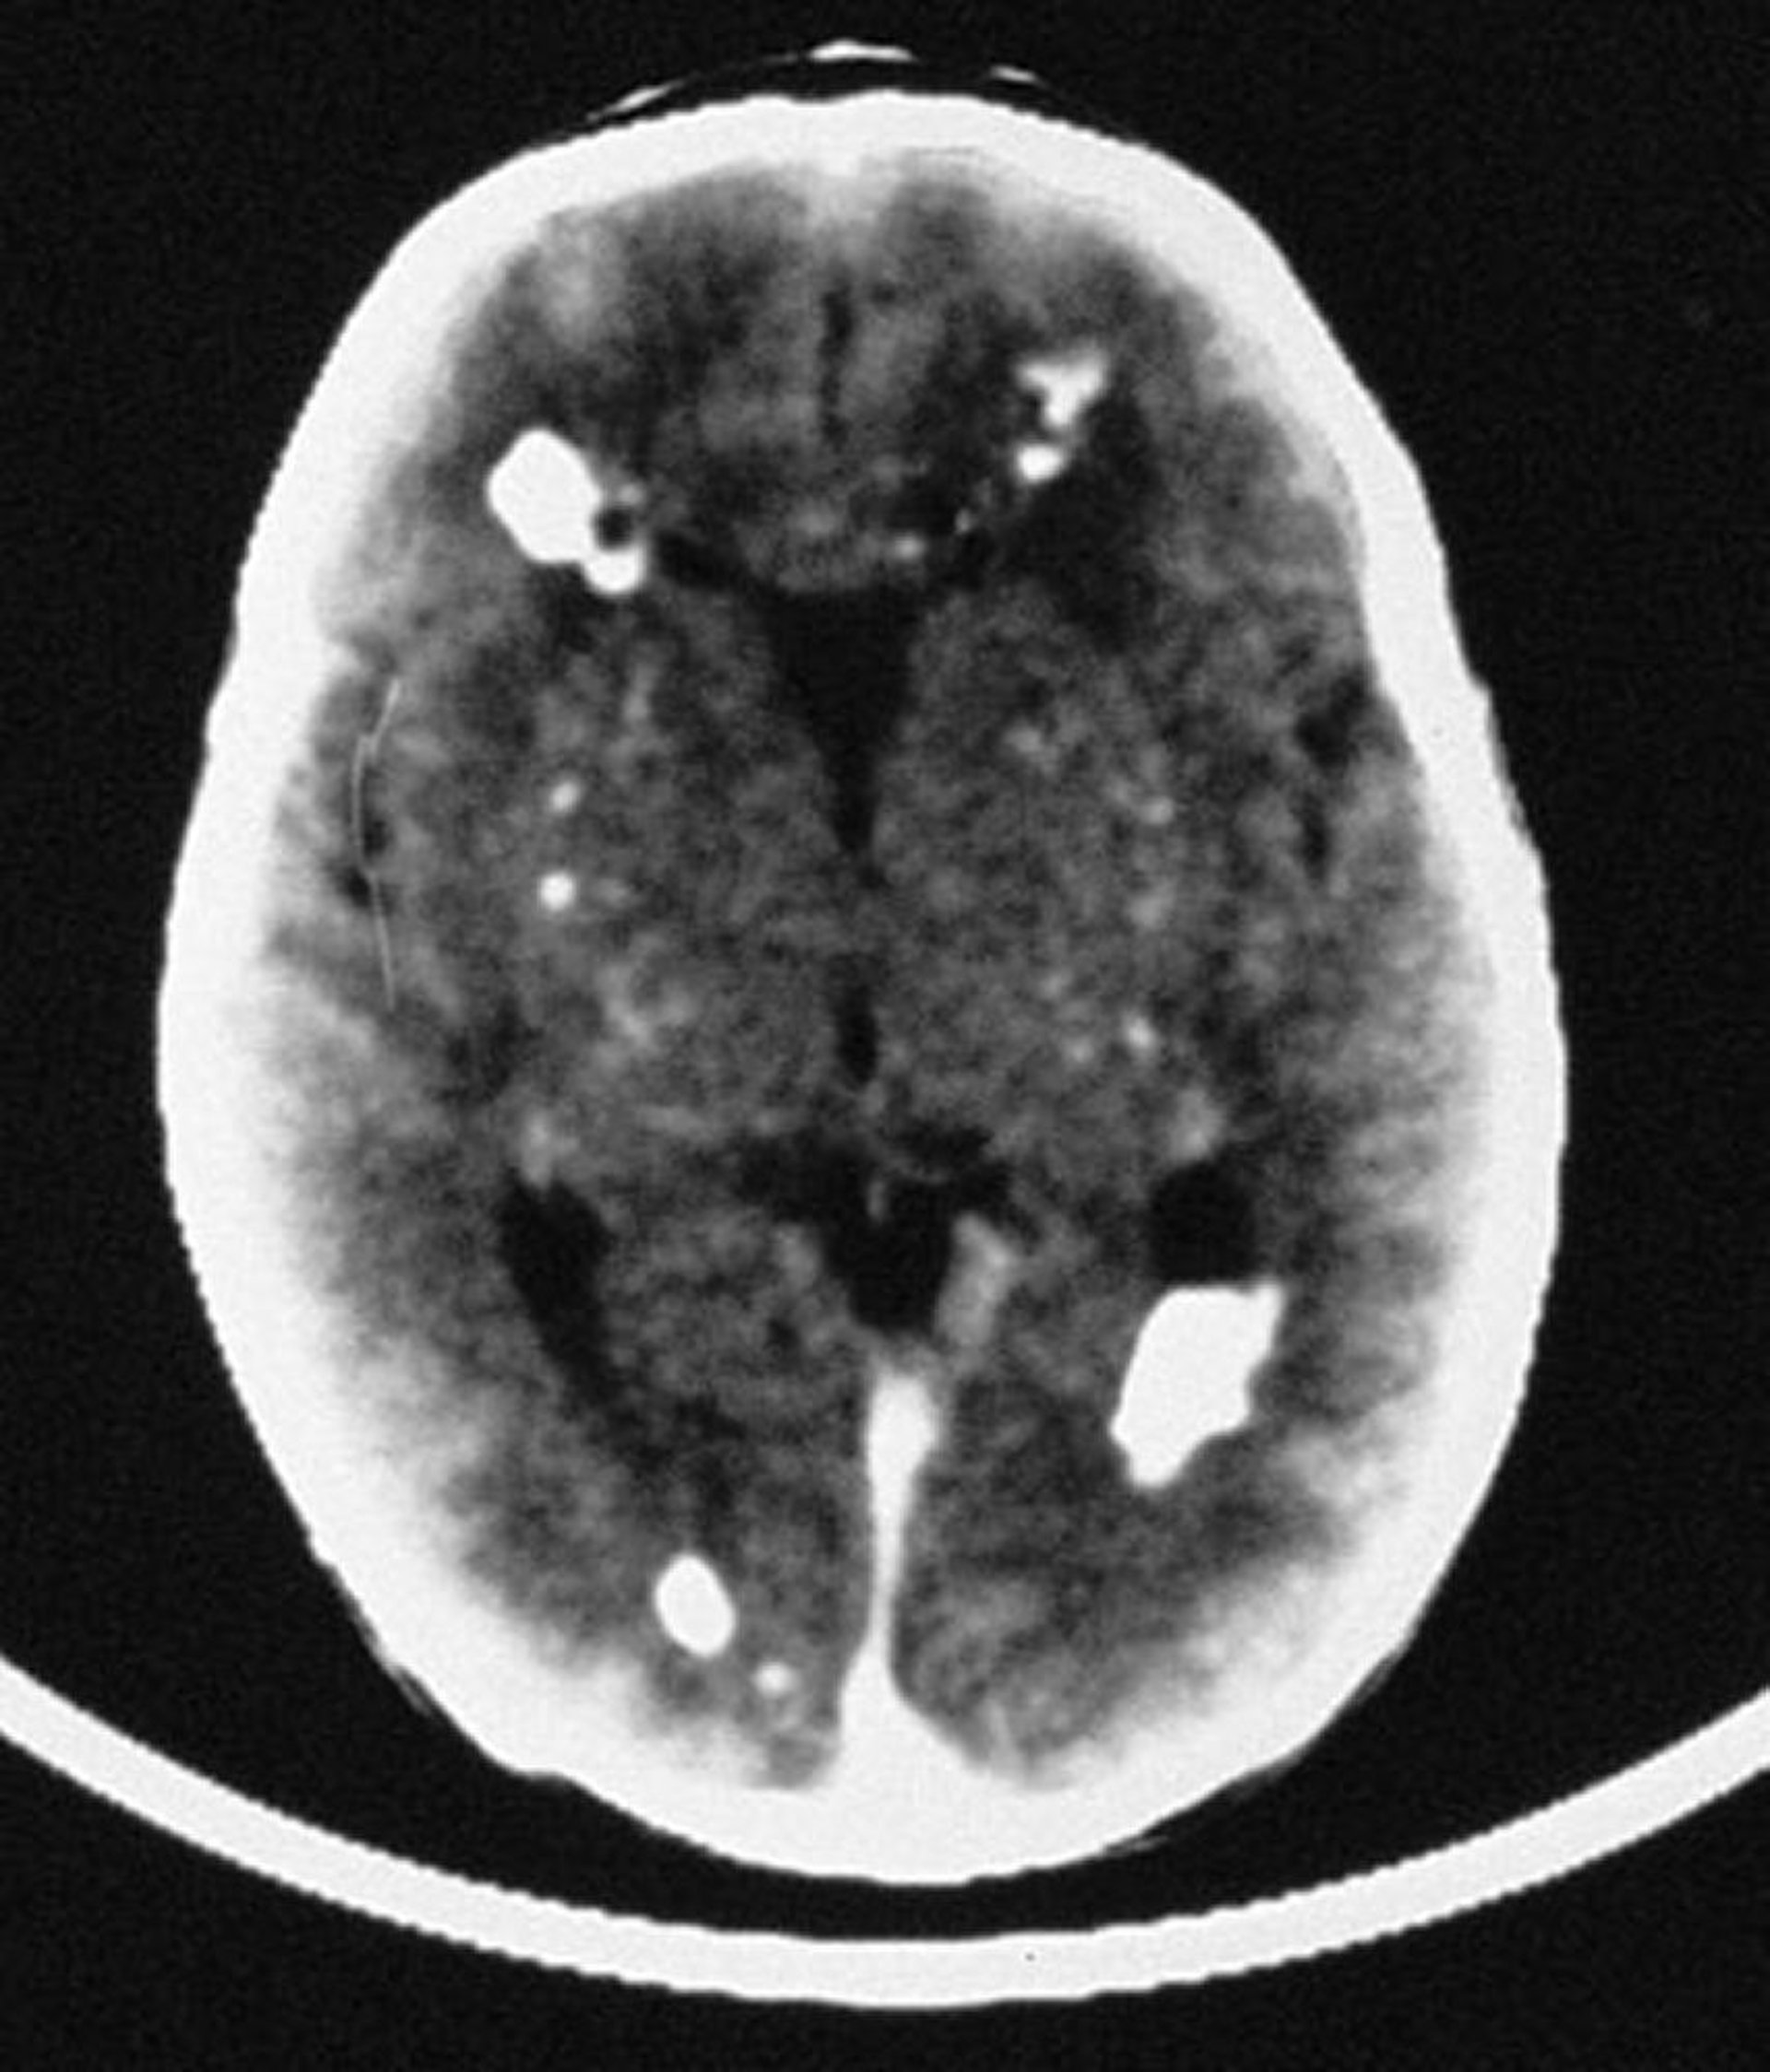

Dans cette image, la TDM révèle de multiples calcifications intracrâniennes, principalement périventriculaires, mais impliquant également des structures vasculaires du cerveau.

By permission of the publisher. From Demmler G: Congenital and perinatal infections. In Atlas of Infectious Diseases: Pediatric Infectious Diseases. Edited by CM Wilfert. Philadelphia, Current Medicine, 1998.